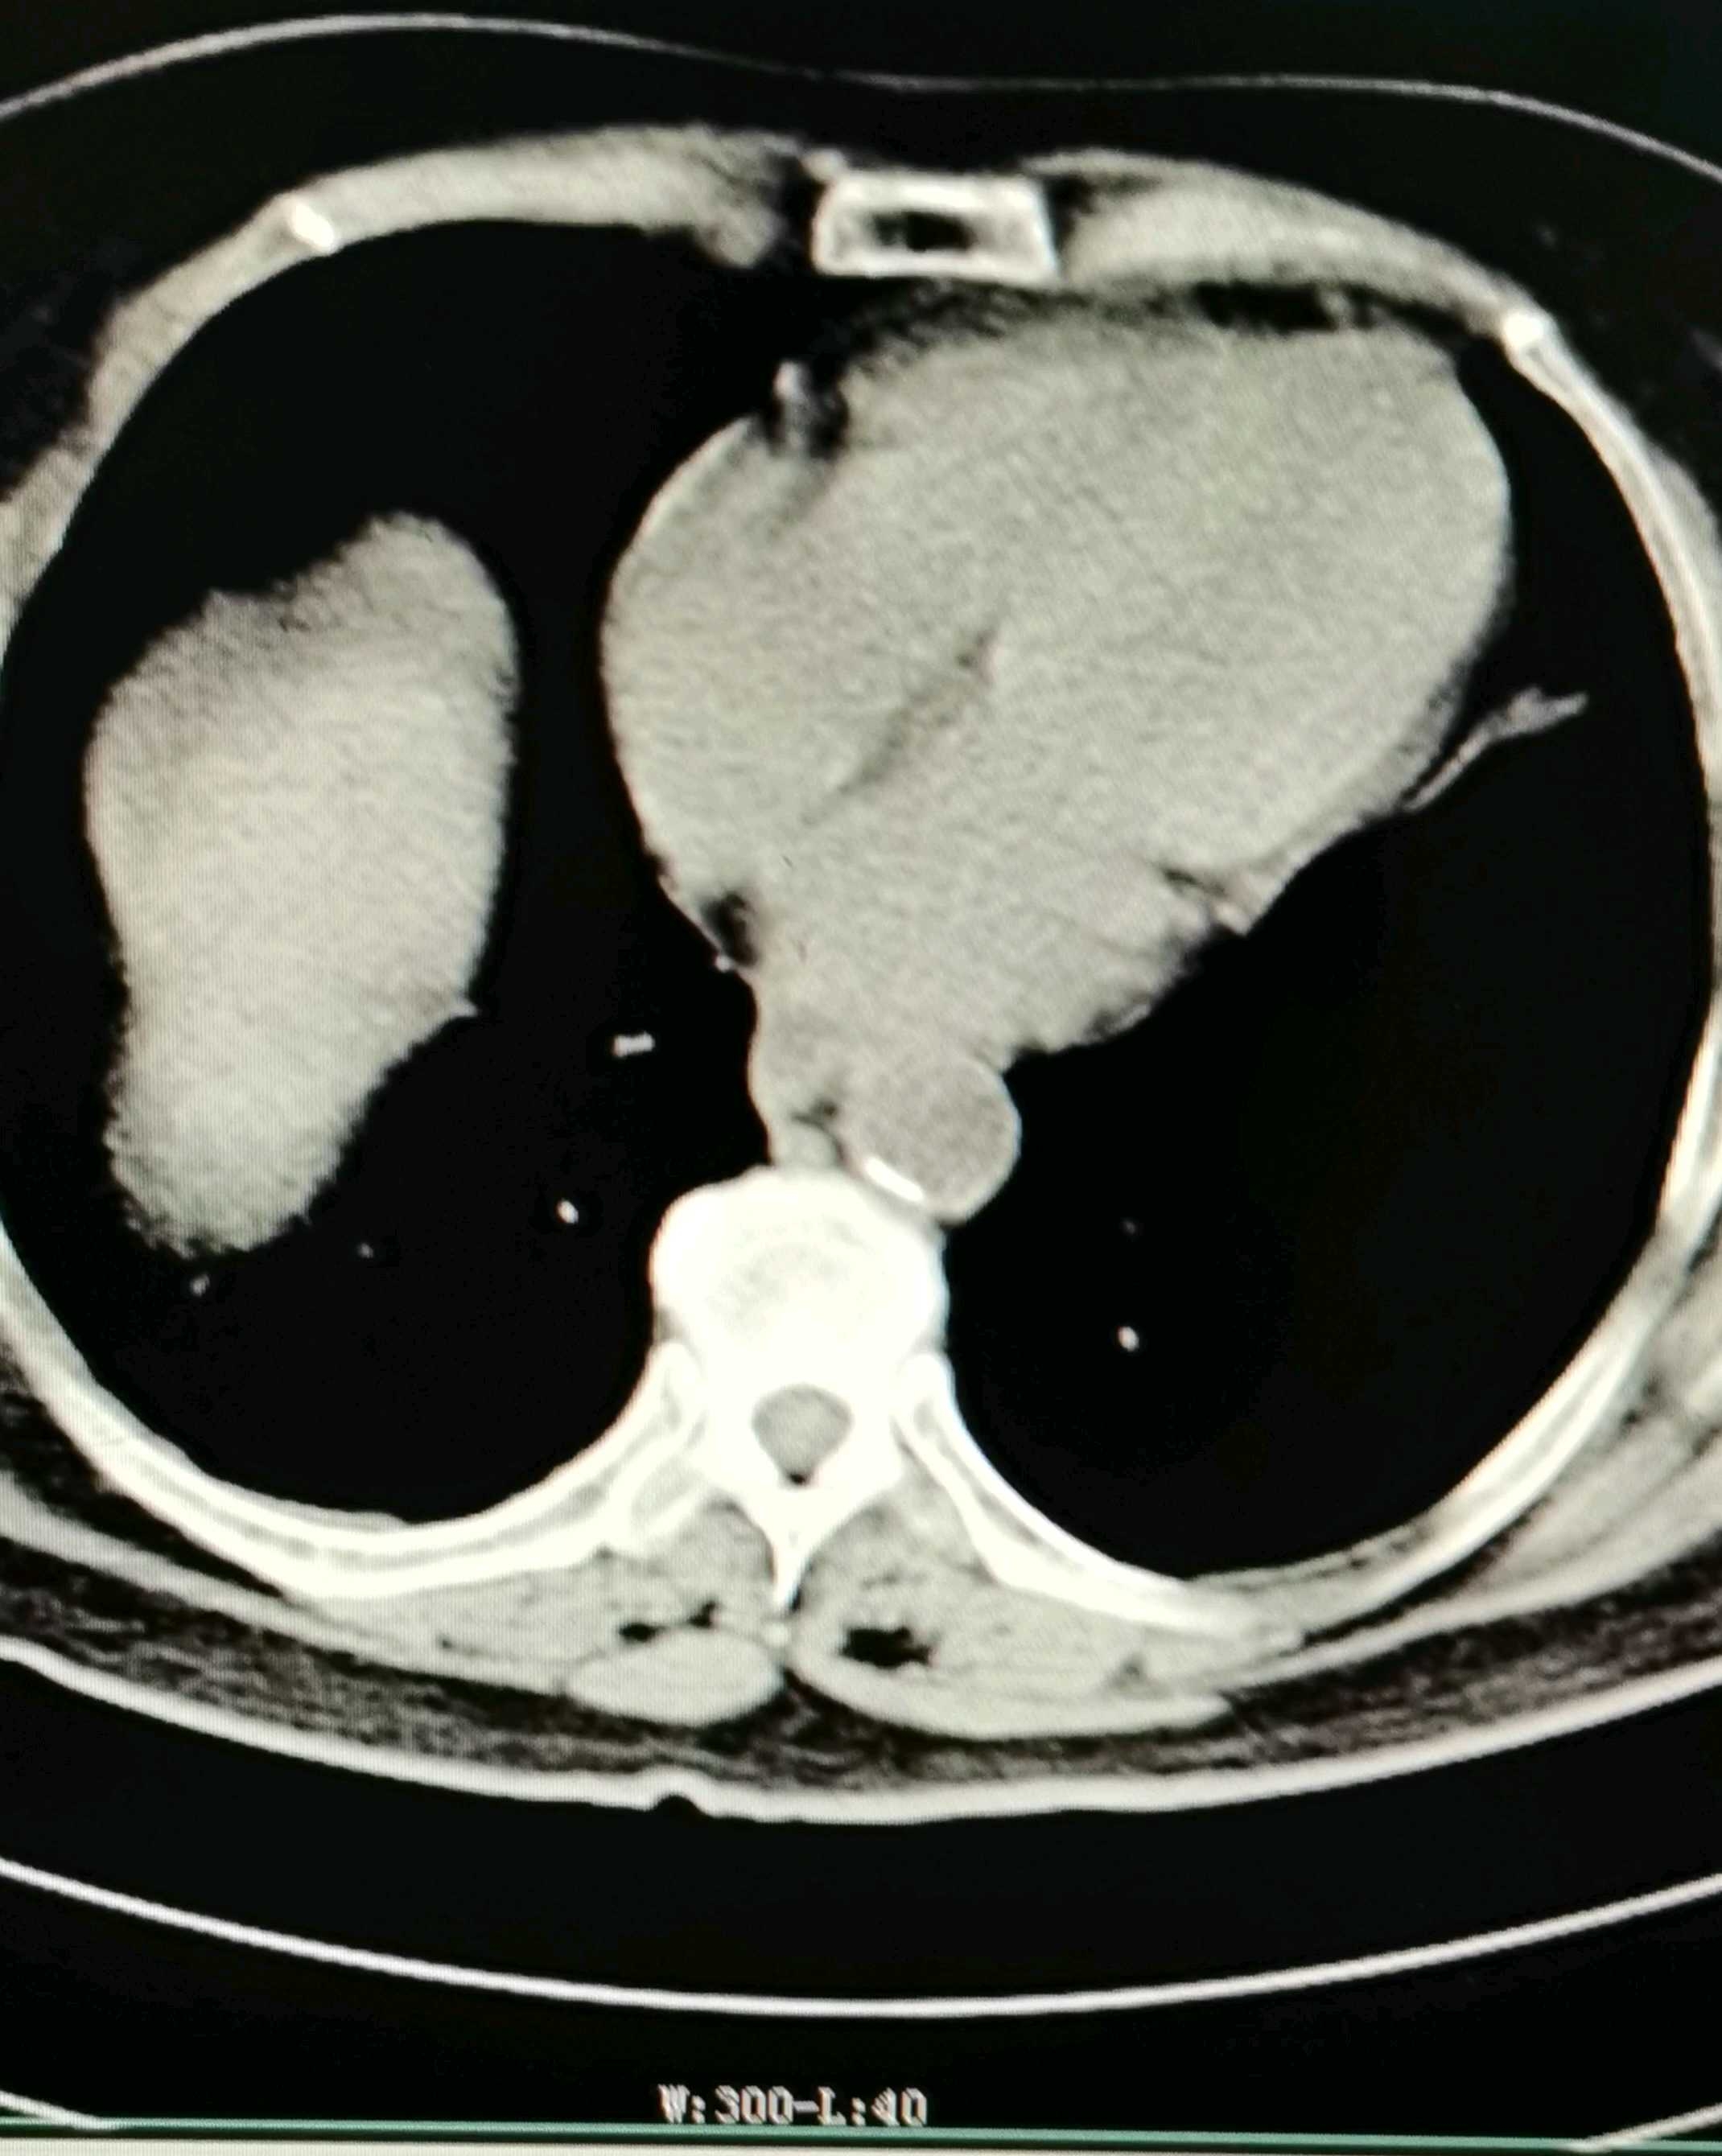

女性,76岁,因腹痛6天入院。既往有糖尿病。无呕血黑便,无发热畏寒,无咳嗽咳痰。精神饮食差,体重无明显变化。血压心率呼吸正常,

这次检查有肝硬化腹水,血红蛋白值53,入院后还是有下降,不清楚血红蛋白低的原因!难道就是肝硬化引起?其实病程已经很长了?老人家描述突发是错误的。恳请老师们指点迷津!望版主推荐帮忙分析!

我的想法是进一步做个大便隐血,抽腹水做常规检查,血液检查乙肝病毒,排除结核。贫血原因是什么?